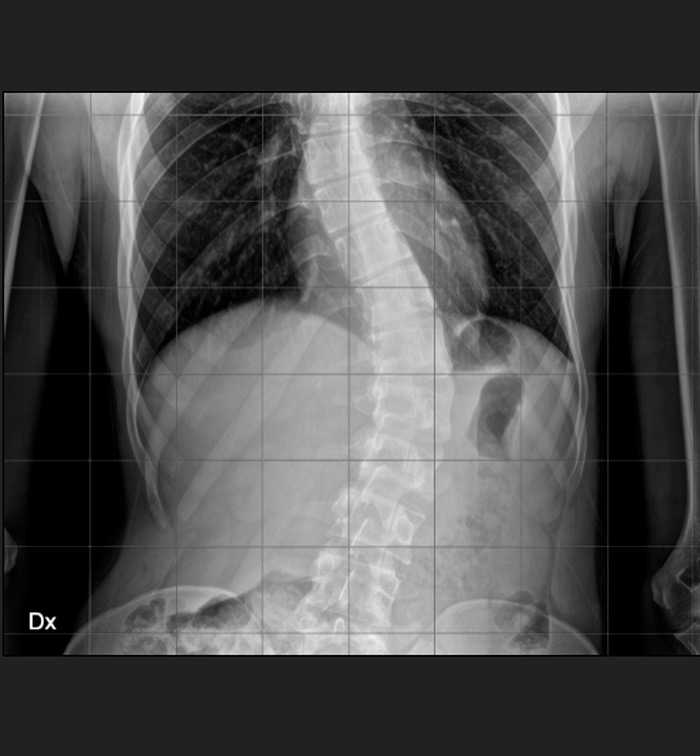

DIAGNOSI:

IPERCIFOSI DORSALE + SCOLIOSI DORSO LOMBARE

Radiografia della colonna in toto pre-operatoria